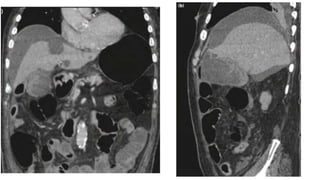

Retroperitoneal (psoas) abscess

• At the start of the twentieth century, psoas abscess was mainly

caused by TB of the spine (Pott’s disease).

• With the decline of M. tuberculosis as a major pathogen in resource-

rich countries,

• a psoas abscess was mostly found secondary to direct spread of

infection from the inflamed ± perforated digestive or urinary tract.

• In recent years a primary psoas abscess due to haematogenous

spread from an occult source is more common, especially in

immunocompromised and older patients, as well as in association

with intravenous drug misuse.

Retroperitoneal (psoas) abscess •At the start of the twentieth century, psoas abscess was mainly caused by TB of the spine (Pott’s disease). • With the decline of M. tuberculosis as a major pathogen in resource- rich countries, • a psoas abscess was mostly found secondary to direct spread of infection from the inflamed ± perforated digestive or urinary tract. • In recent years a primary psoas abscess due to haematogenous spread from an occult source is more common, especially in immunocompromised and older patients, as well as in association with intravenous drug misuse.